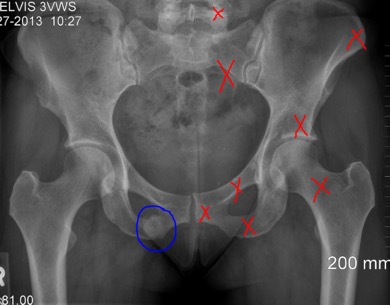

View Pubic Bone Fracture Treatment Pics. A bone fracture (abbreviated frx or fx, fx, or #) is a medical condition in which there is a partial or complete break in the continuity of the bone. The pubis itself is made up of two smaller bones:

The pubic bone is the front bone portion of the pelvis or pelvic crest in the lower abdomen.